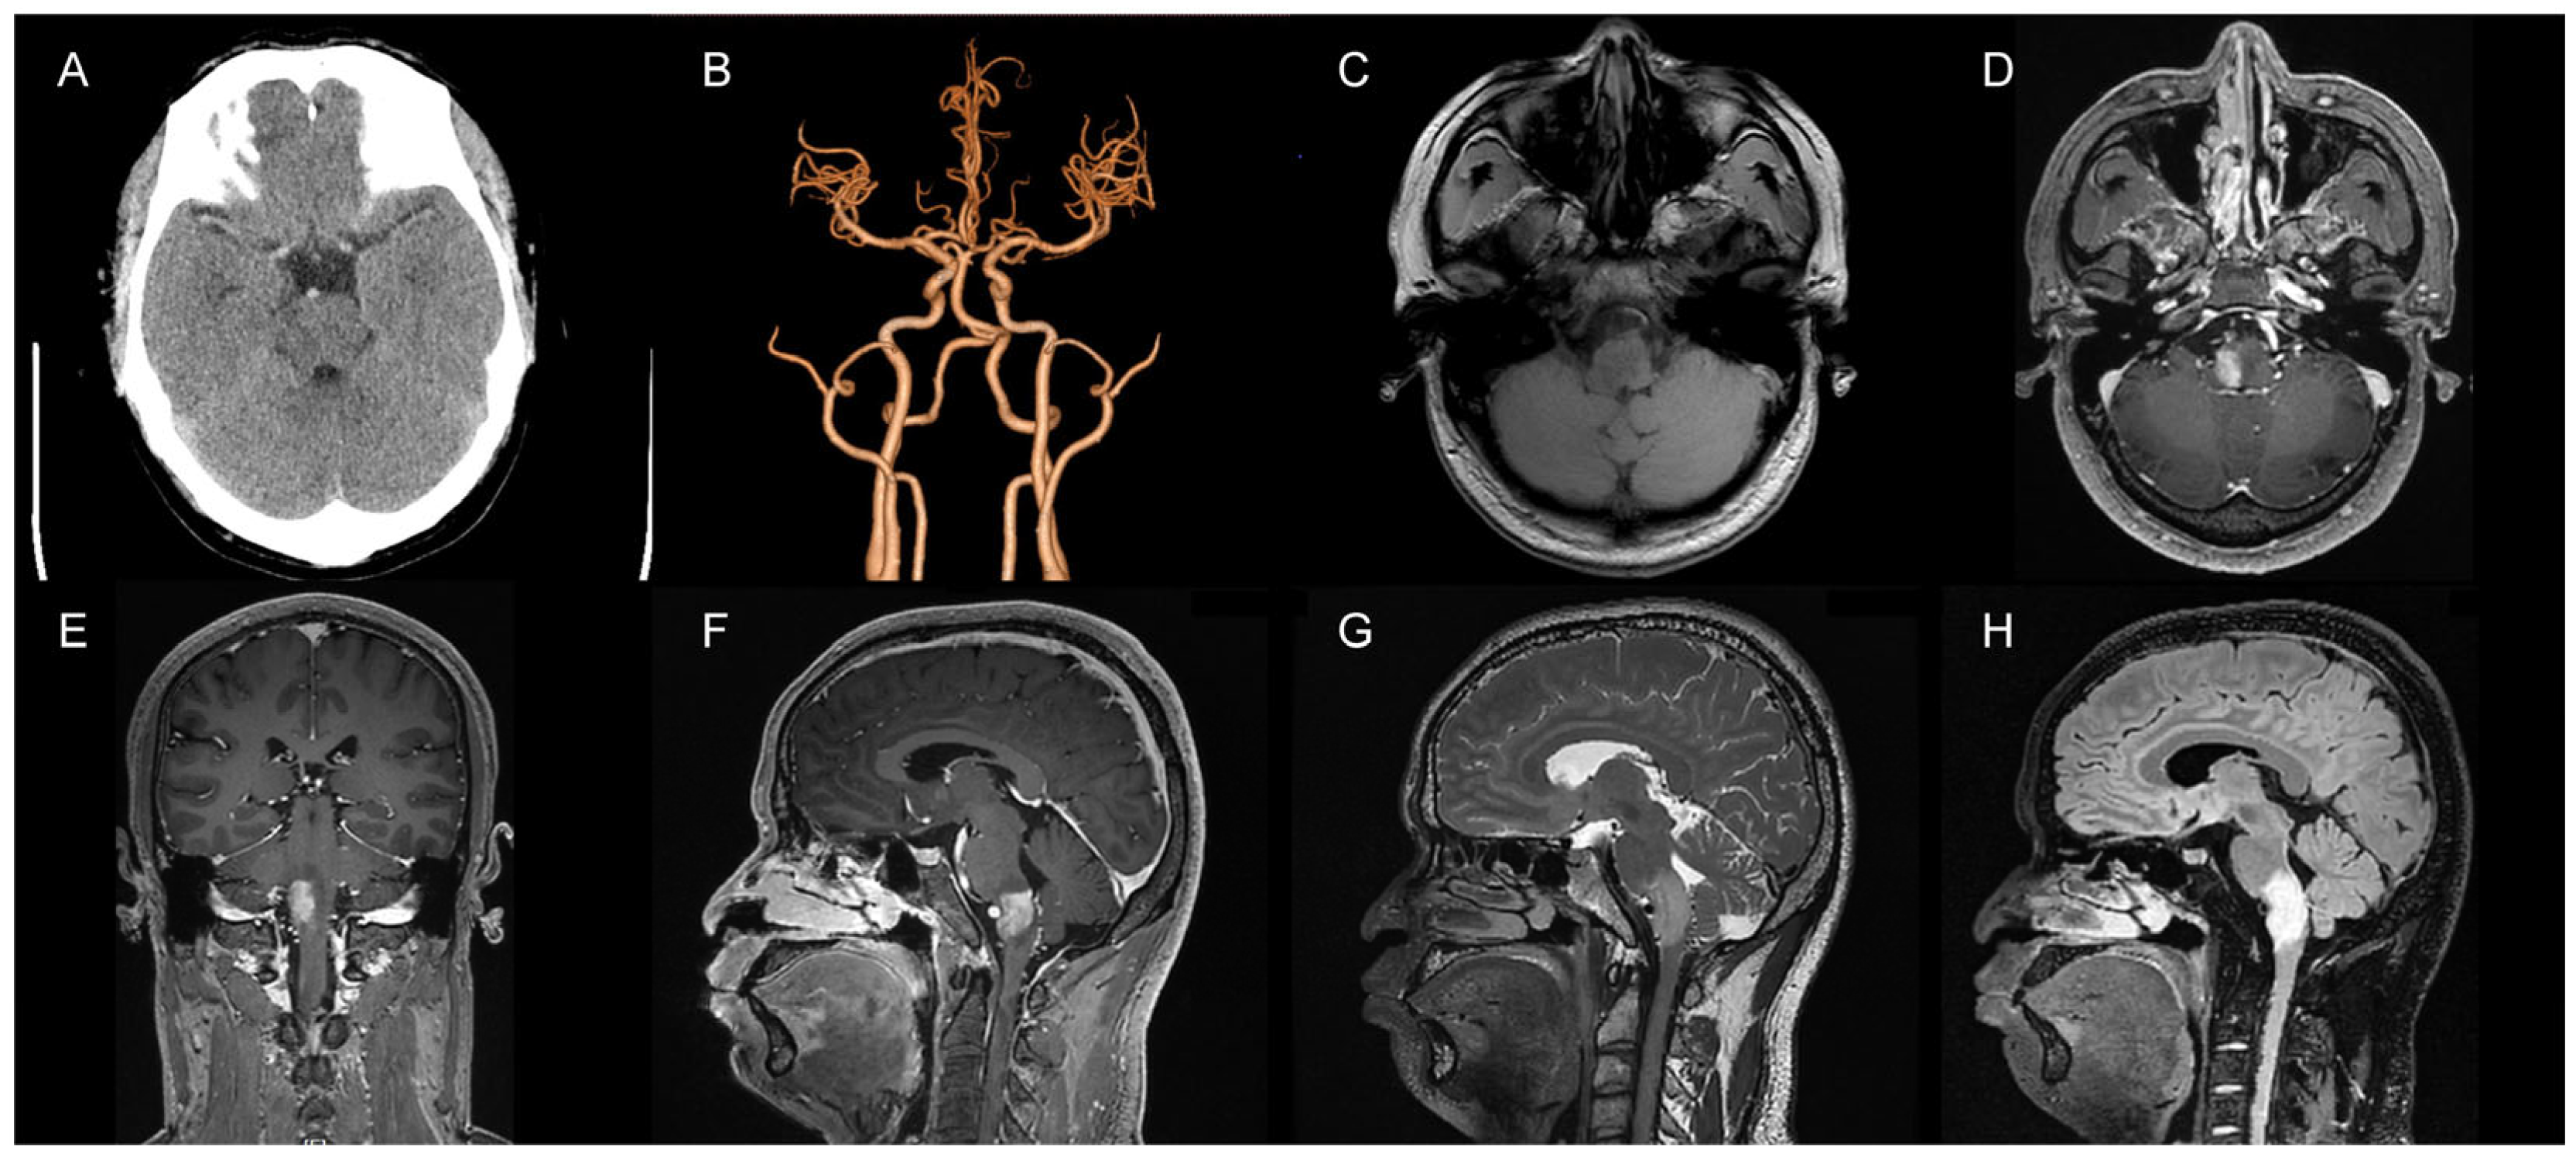

The patient (34-year-old male) was admitted to the hospital with “intermittent headache with hoarseness for 10 days”. The patient experienced intermittent headache 10 days prior, which was intense during the attack but subsided after taking rest, accompanied by hoarseness. The patient did not experience dizziness, nausea, vomiting, weakness of the limbs, twitching of the limbs, difficulty in swallowing, or choking while drinking. A physical examination showed that his consciousness was clear, and his speech was fluent but slightly hoarse. Both pupils (2.5 mm in diameter) were equal in size and round and responsive to light, the muscle strength of the limbs was grade V, and the muscle tone was normal. The patient was admitted to the hospital and underwent routine imaging tests. Computed tomography (CT) examinations suggested an abnormal brainstem density (Figure 1A), and CT angiography (CTA) examinations showed no significant abnormalities (Figure 1B). We tentatively diagnosed the cause as a brainstem tumor and initially suggested craniotomy to remove the mass lesion. The cranial magnetic resonance imaging (MRI) scan showed lamellar, slightly long T1 and slightly long T2 signal intensities in the brainstem, with a maximum area of about 19 mm × 19 mm in the transverse position. The area of the lesion increased significantly after enhancement (Figure 1C–G). The Flair sequence showed a strong signal (Figure 1H). The MRI examinations suggested the presence of a lamellar abnormal signal in the brainstem with a vascular flow space shadow. There were prominent vascular markings anterior and posterior to the brain stem on MRI (high signal with contrast and voids on T2 images), which pointed to the possibility of AVF.

Figure 1.

Preoperative imaging. (A) A CT examination suggested abnormal brainstem density; (B) CTA showed no significant abnormalities; (C) Abnormal brainstem signal in the T1 sequence; (D) T1 enhancement suggested significant enhancement at the site of the lesion (axial view); (E) T1 enhancement suggested significant enhancement of the focal area (coronal view); (F) T1 enhancement suggested significant enhancement at the site of the lesion (sagittal view); (G) A T2 sequence with a slightly long signal in the brainstem and vascular flow space shadow in the focal area; (H) The Flair sequence suggested a high signal at the focal area.